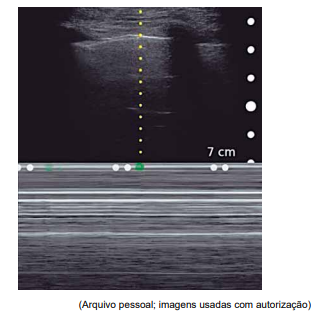

Paciente de 2 anos, internado em UTI pediátrica por insuficiência respiratória aguda secundária à pneumonia extensa. Intubado com cânula orotraqueal número 4 com cuff, com bom padrão respiratório, mantendo SatO2 = 96%. Logo após atendimento da fisioterapia, apresentou queda de saturação sustentada até 70% e assincronia ventilatória. Exame físico com ausculta muito diminuída em hemitórax direito, com expansibilidade também diminuída no mesmo lado. Associado a isso, houve queda de PA para 66 x 24 (44) mmHg e piora da perfusão.

Realizou-se a ultrassonografia “point-of-care” conforme imagem a seguir, no modo M, vista em todo hemitórax direito (aspecto de “código de barras”).

Enunciado 4425056-1

Considerando esses achados, qual é a conduta adequada para a condição apresentada pelo paciente?